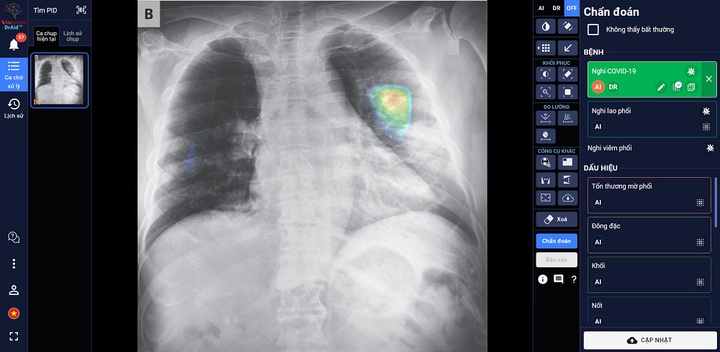

DrAid™ – phần mềm AI trợ lý bác sĩ đầu tiên tại Việt Nam - do các chuyên gia, nhà khoa học của VinBrain (công ty công nghệ thuộc Tập đoàn Vingroup) nghiên cứu phát triển thành công. DrAid hiện có khả năng hỗ trợ chẩn đoán 20 dấu hiệu bất thường và bệnh lý về tim - phổi - xương với độ chính xác trên 88% trong vòng 5 giây, đồng thời tự động đưa ra báo cáo y tế theo chuẩn quốc tế JCI có khoanh vùng và đo kích thước chính xác tại khu vực bất thường.

Đặc biệt, DrAid™ mang lại 4 giá trị ưu việt trong phát hiện và điều trị COVID-19 dựa trên ảnh X- quang ngực thẳng gồm: Phát hiện nhanh góp phần sàng lọc mầm bệnh trong cộng đồng, song song cùng phương pháp xét nghiệm PCR. Kết hợp cùng xét nghiệm PCR từ đó nâng cao độ chính xác, giảm thiểu tình trạng âm tính giả tránh bỏ sót; Hỗ trợ đánh giá tiên lượng tình trạng bệnh nhân thông qua lịch sử hình ảnh chụp X-quang, để từ đó có hướng điều trị phù hợp; Hỗ trợ tăng tính nhất quán và chuyển giao kiến thức của bác sĩ từ tuyến Trung ương tới cơ sở.

DrAid™ chẩn đoán và tiên lượng điều trị bệnh nhân COVID-19 dựa trên hình ảnh X-quang ngực thẳng.